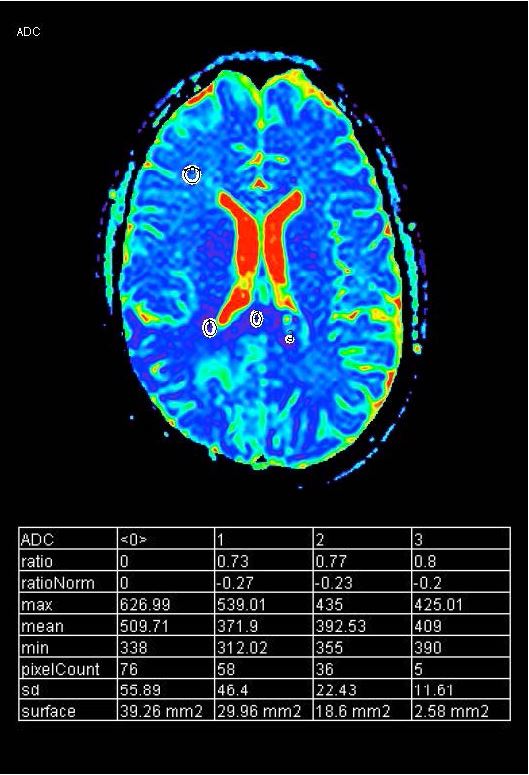

На T2 зона гіперсигналу була видна в передньо-нижній зоні від резекційної порожнини з нечітким контрастним посиленням, а також на мозолистому тілі, яке чітко збільшене порівняно з зображеннями FU МРТ за 1 місяць до (рис. 5 і 6). Це ураження показало обмеження дифузії (рис. 8).

Рисунок 8 ADC map lesion